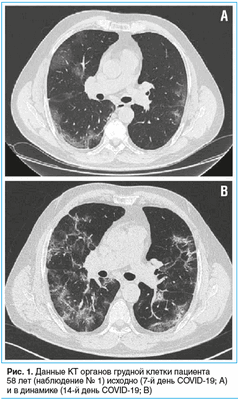

Пациент 58 лет был госпитализирован в инфекционное отделение с вероятным диагнозом COVID-19. За неделю до госпитализации возник сухой кашель, имело место повышение температуры тела до 38,0 °C. При компьютерной томографии (КТ) органов грудной клетки выявлены двусторонние интерстициальные изменения легочной ткани по типу матового стекла, поражение легочной ткани составило 68% (рис. 1А).

Пациенту была назначена терапия азитромицином, гидроксихлорохином, дексаметазоном и эноксапарином натрия, проводилась кислородотерапия (при инсуффляции кислородом SpO2 95%). Диагноз COVID-19 был подтвержден положительным результатом исследования орофарингеального мазка на SARS-CoV-2, выполненного методом полимеразной цепной реакции в реальном времени (ПЦР-РВ). В последующем этиотропная терапия была заменена на лопинавир/ритонавир и интерферон β-1b в связи с развитием одышки, увеличением общего объема поражения легочной ткани до 80% и появлением свежих участков интерстициальных изменений в легких при повторной КТ органов грудной клетки (рис. 1B).

На 3-й день от начала терапии ВВИГ появилась осиплость голоса без нарастания одышки, но улучшились значения лабораторных показателей: нормализация содержания CРБ (1,0 мг/л), повышение уровня лимфоцитов (1,02×10 9 /л). На КТ органов грудной клетки — положительная динамика в виде значительного снижения плотности, уменьшения протяженности изменений в легких с наличием линейных консолидаций преимущественно в задних отделах легких, объем поражения уменьшился до 65%. После завершения курса терапии ВВИГ у пациента появились галлюцинации, дезориентация в пространстве и времени, дестабилизация гемодинамики с тахикардией 130 уд/мин, снижением АД до 65/30 мм рт. ст., тахипноэ (ЧДД 38 в минуту) с SpO2 68%, хрипы в легких, макрогематурия. Была начата инвазивная вентиляция легких (ИВЛ), инотропная поддержка допамином, норэпинефрином.